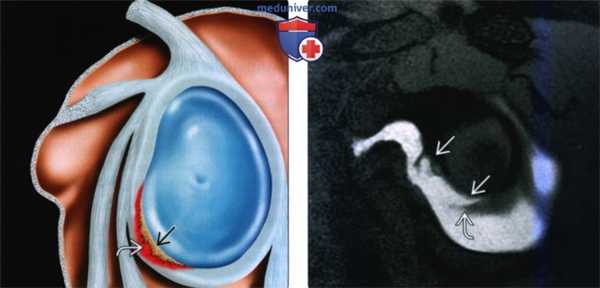

(Слева) На сагиттальном рисунке показано повреждение Банкарта с отделением передненижней губы. Имеется кровотечение (изображено красным) в области разрыва В, указывающее на свежую травму Наиболее частым местом повреждения Банкарта является губно-суставное хрящевое соединение у суставного края.

(Справа) На косой сагиттальная МР артрограмме Т1 FS видно повреждение Банкарта у пациента с передним вывихом в анамнезе. Видна часть отделенной передней губы.